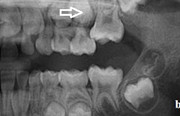

Vali sind huvitav pilt ja me näitame sellega seotud haigust ja sümptomeid